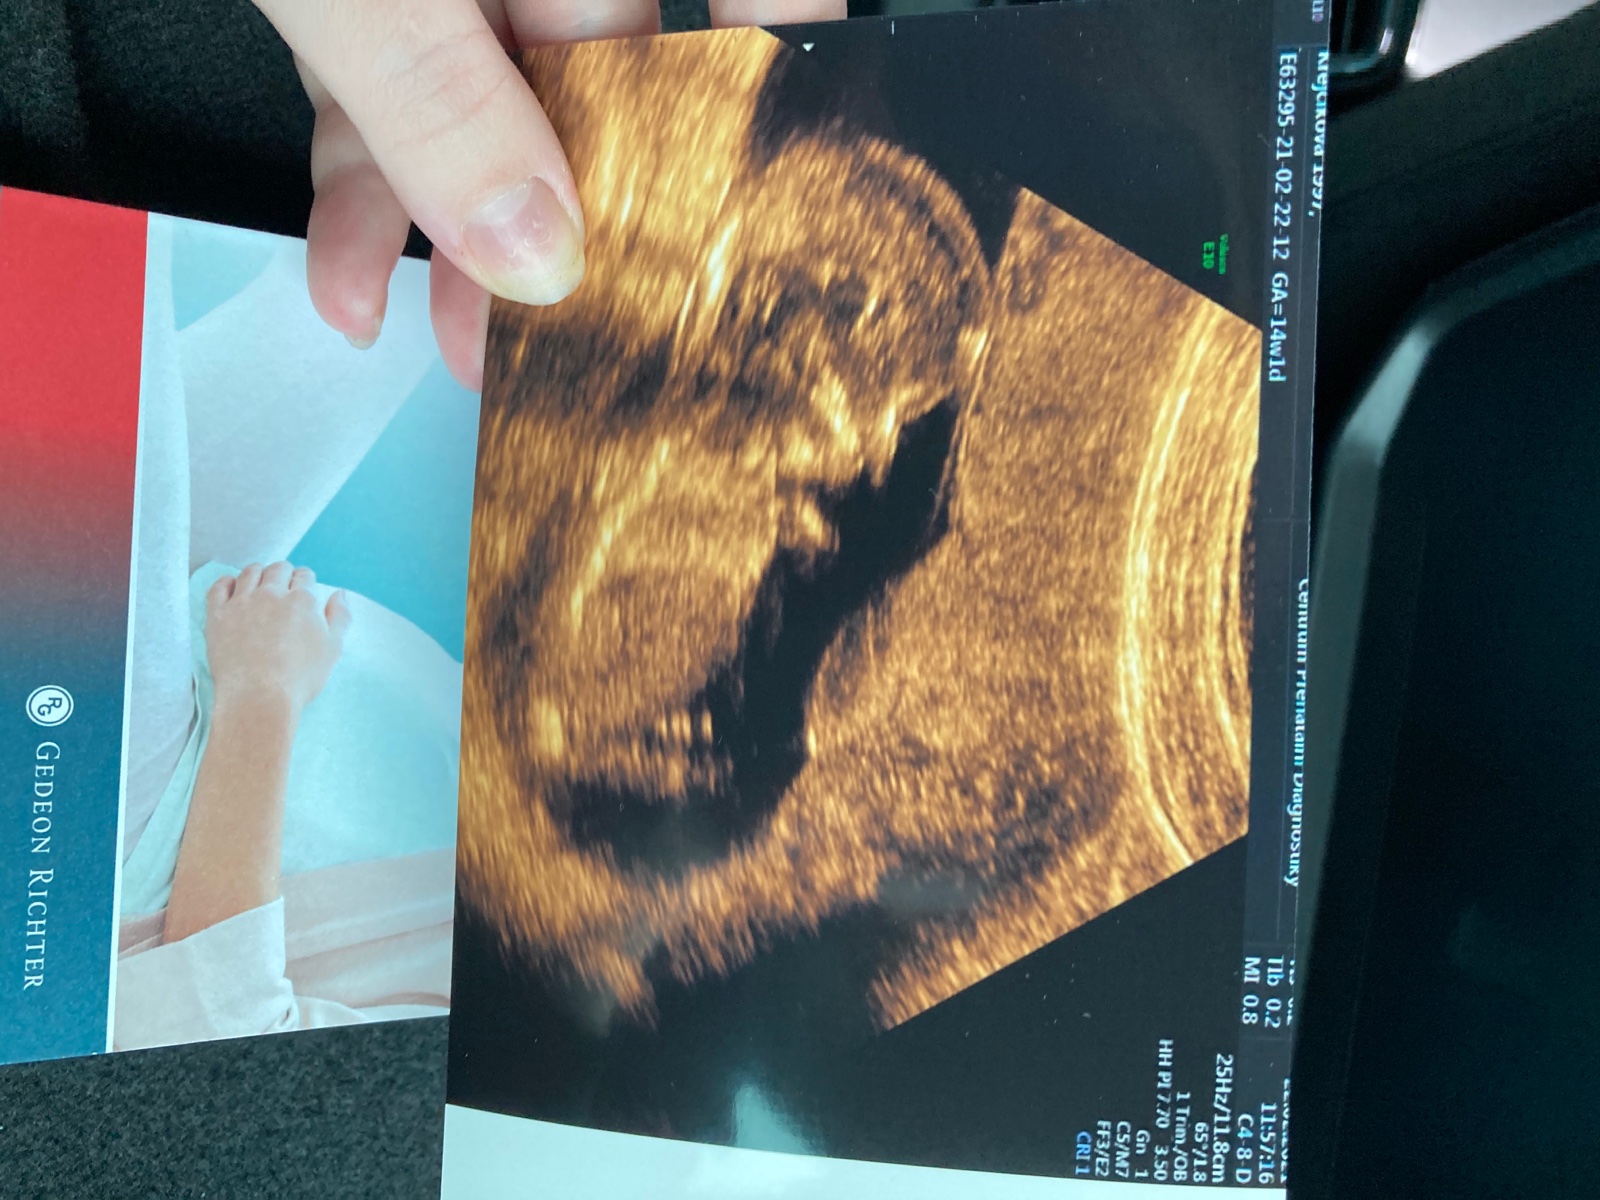

@misak48 ani nemluvte. Ultrazvuk vysel pekne, ale krev spatne, takze celkovy vysledek vysel na hrane a museli jsme do nemocnice na podrobnejsi ultrazvuk....naprosto nas to vystresovalo, tam to nastesti dopadlo dobre, melo by to byt v poradku 🙈 toto tehotenstvi si "uzivame" nejdrive potrat, pak na zacatku tehu covid, pak nejaka strevni bakterie a viroza, pak na ultrazvuku nebyl videt plod a ted zase screening 🙈 asi me odvezou.